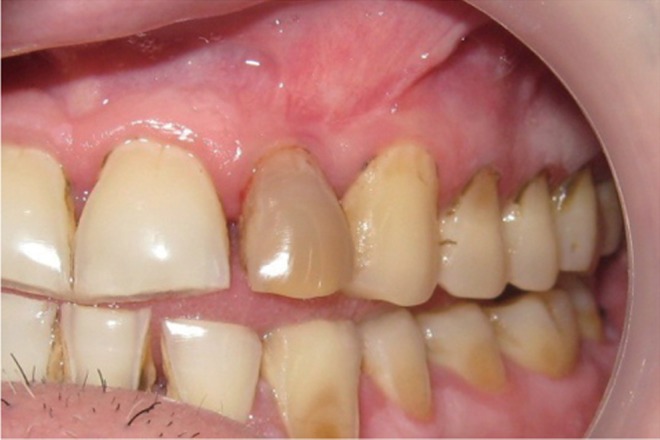

A 35 year old male patient reported to the Department of Periodontics with a complaint of pain in the upper left front tooth region associated with pus discharge for 2 months (

Figure 1). He also gave history of trauma around 7 years back and noticed discoloration of tooth with time but he took no treatment as the tooth was asymptomatic. On intraoral examination there were no carious teeth. Intraoral periapical X-ray (IOPA) was taken which revealed radiolucency along the distal side of the entire root surface to the apex (

Figure 1Preoperative view of discoloured maxillary lateral incisor.